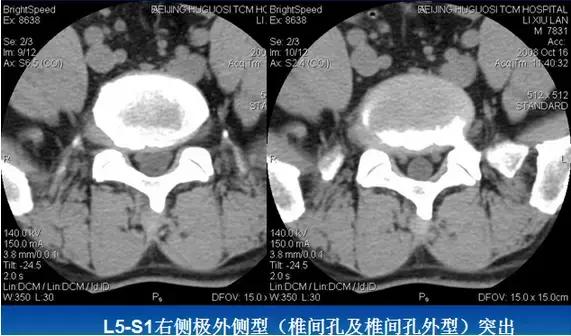

⑶后外侧型:椎间盘影于椎间孔方向局限性超出椎体边缘,神经根受压,椎间孔、侧隐窝变窄。

⑷远外侧型:椎间盘影于椎管外局限性超出椎体边缘,多伴纤维环钙化,骨赘形成,脊神经、周围肌肉、韧带受压移位。